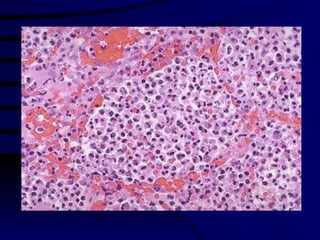

Lymphnode Biopsy Large cells Mitotic figures

Histiocytic/Tcell NHL Diffuse pattern – no follicles. Large cells with moderate cytoplasm Plenty of mitotic figures, Nuclei are vesicular prominent nucleoli Features suggest T-cell NHL – malignant lymphoma. Needs further marker studies for typing & management. cancer Chemotherapy.

Lymphnode Biopsy Largecells Mitotic figures

Histiocytic/Tcell NHL Diffusepattern – no follicles. Large cells with moderate cytoplasm Plenty of mitotic figures, Nuclei are vesicular prominent nucleoli Features suggest T-cell NHL – malignant lymphoma. Needs further marker studies for typing & management. cancer Chemotherapy.